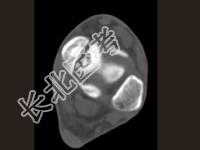

- 单项选择题男,17岁, 踝关节疼痛,关节作响, 结合图像,最可能的诊断是 ( )

B、剥脱性骨软骨炎